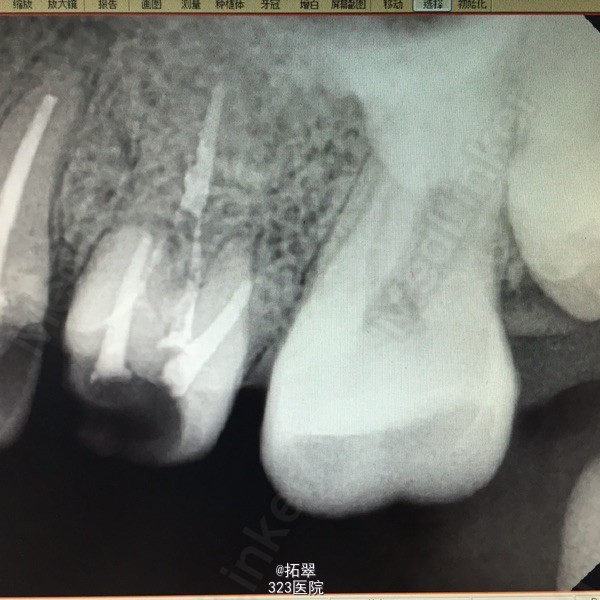

诊断:左上6尖周炎 左上5慢性牙髓炎 建议:左上6根管再治疗后+桩+冠修复 左上5RCT+桩+冠 处理:左上6拆冠,清理根管,MB、DB长16mm,扩至F1,P长17mm,扩至F1,双氧水反复冲洗,木馏油棉开放 左上5开髓,置乳失,丁香油棉安抚,ZOE暂封。

后期患者无不适,治疗完善。